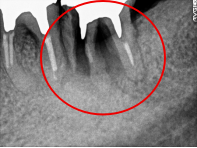

Before

※赤丸を抜歯しました。

After